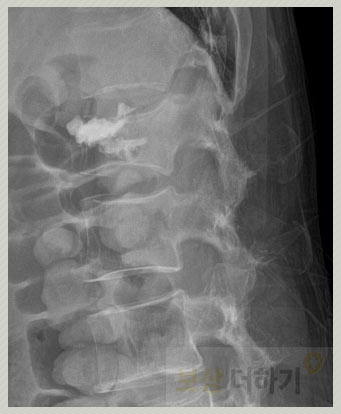

요추 골절 1번 (S32020)

허리뼈(요추)가 위아래로 눌려 부서지거나 납작해지는 골절 형태를 말합니다. 요추 1번에서 가장 흔히 발생하며 특히 골다공증이 있는 노년층에서 자주 나타납니다. 미끄러지거나 교통사고, 무거운 물건을 갑자기 들어올릴 때처럼 허리에 직접적으로 강한 힘이 가해지는 경우 또는 장기간의 잘못된 자세나 반복적인 압력으로 뼈가 점차 약해지면서 발생하기도 합니다.

L1 부위의 골절, 폐쇄성 S32020 (Fracture of L1 level, closed)